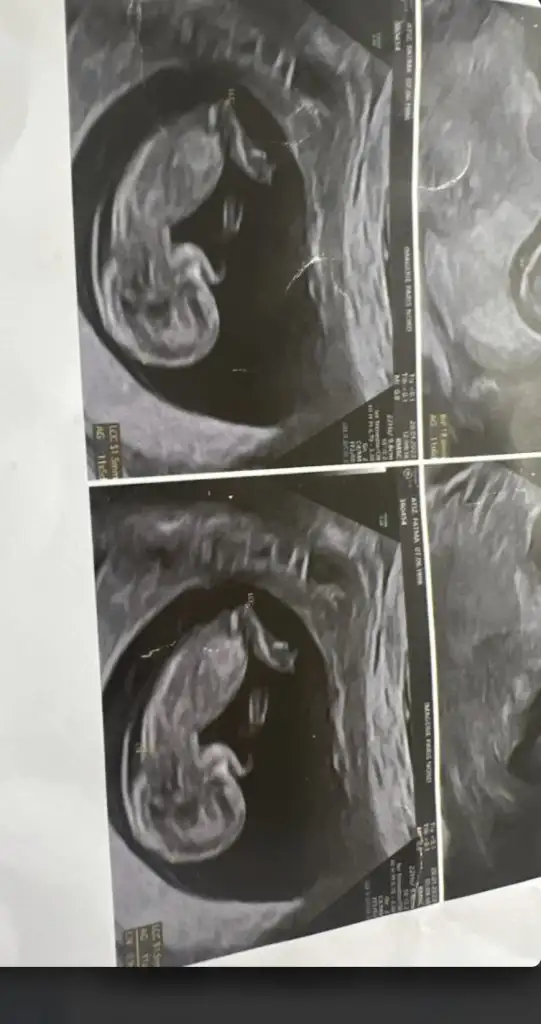

Bu foto 11haftalik cnmFoto atarmisniz gorunuyosa nubdan tahmin edilir

Nubu tam net gorunmuyo kapatmis ama kafa yapisi kiza benziyo yuvarlak kiz olma ihtimali yuksekBu foto 11haftalik cnm

Nubu tam net gorunmuyo kapatmis ama kafa yapisi kiza benziyo yuvarlak kiz olma ihtimali yuksek

Peki bu resimdeNubu tam net gorunmuyo kapatmis ama kafa yapisi kiza benziyo yuvarlak kiz olma ihtimali yuksek

Doktor kiz oldugunu soylemis olmali bacak arasi bos cnku